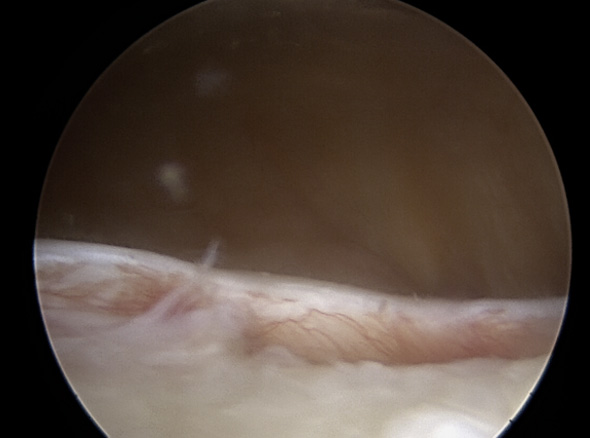

관절 내시경을 통해 늘어나 있는 관절낭을 알맞은 긴장도를 갖도록 봉합하여 줍니다.

이러한 경우

관절낭 중첩술을

고려합니다.

다방향성 불안정증